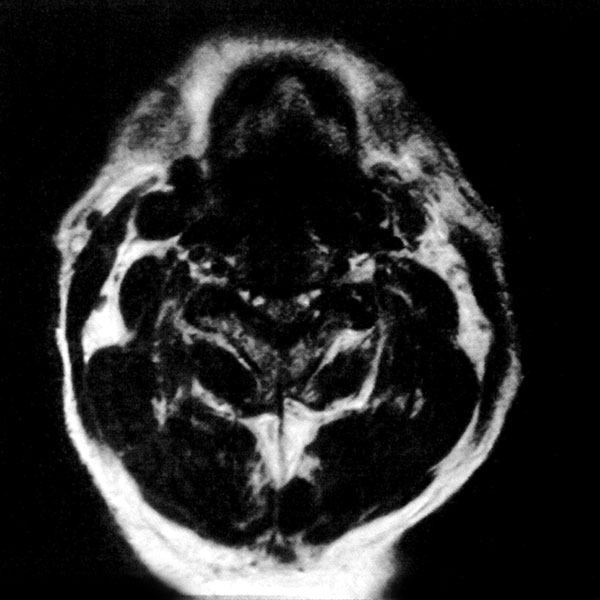

MRI検査

2025年9月16日スタート!!1.5T MRI SIGNA Creator(GE社製)

新しいMRI装置では従来の装置と比較し、高画質、かつ短時間での検査が可能となります。

狭い場所での検査が苦手な方にも優しい設計となっておりますので、検査をしたいけど悩まれている方は一度ご相談ください。

- ラッパ型の開口部:閉所恐怖症の方もご相談ください

- 短時間撮像:医師に相談して10 分弱で検査することも可能です

- AI 機能を搭載:従来の装置と比べかなりの高画質が期待できます

- 従来の装置では難しかった微細な変化の描出にも期待がもてます

- PROPEELR 機能により、動きを抑えたきれいな画像が得られます